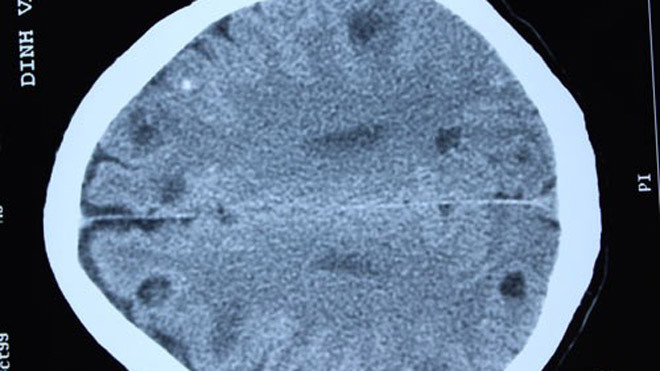

Một lát chụp CT não của bệnh nhân phát hiện nhiều sán đang làm tổ trong não.

Không nằm ngoài dự đoán, kết quả chụp CT sọ não của bệnh nhân cho thấy rất nhiều sán trong não. Nhìn kết quả chụp các bác sĩ cũng phải tá hóa bởi mỗi lát cắt chụp não phát hiện 4 - 5 ổ sán não, trong não của bệnh nhân có tới trên dưới 50 ổ sán não làm tổ.